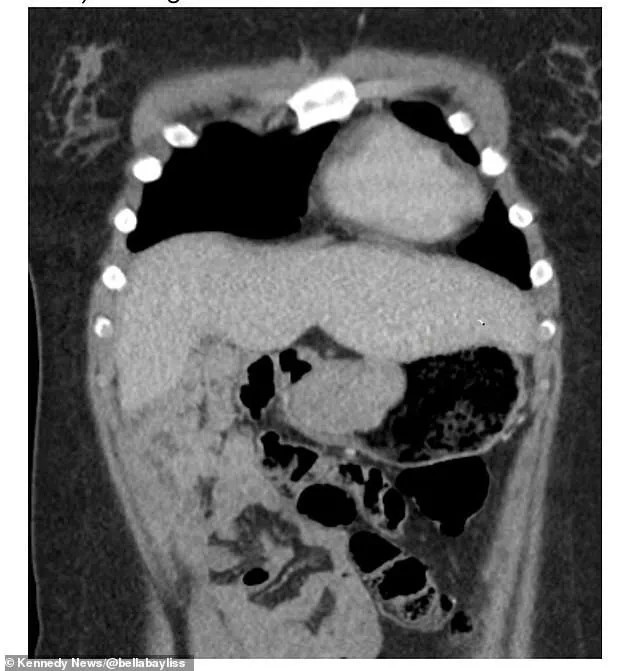

The results were damning: a 6cm gastrointestinal tumor (GIST) had been growing in her stomach. 'If they hadn't left me for so long, I wouldn't have had to have that much of my stomach removed because the tumour got bigger within that time,' she said, her words echoing the regret of a young woman who had been ignored for months.

GIST, or gastrointestinal stromal tumors, is an exceptionally rare form of cancer, affecting only 10-15 people per million annually.

It accounts for just 1 to 2 percent of all gastrointestinal cancers.

Unlike many other cancers, GISTs are caused by sarcomas—malignant tumors that originate in connective tissues such as bone or muscle.

In this case, the sarcoma had taken root in the digestive system.

The symptoms Bella experienced—abdominal pain, feelings of fullness, nausea, and chest discomfort—were all classic signs of the disease, yet they had been overlooked in her initial visit. 'It's a very complex type of cancer,' she said. 'What I have is so rare it doesn't react to standard chemotherapy.' The surgery to remove the tumor was both life-saving and life-altering.